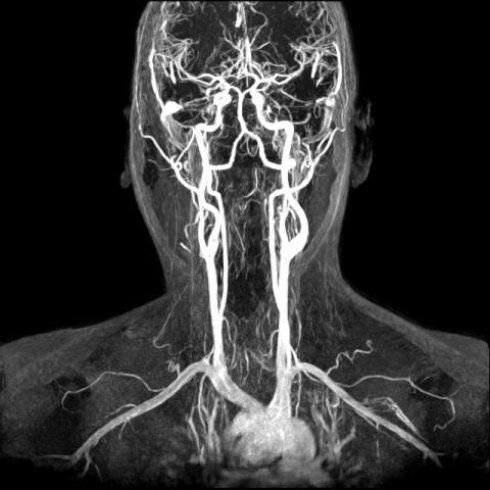

• Angio Rm Del Distretto Vascolare Intracranico anche Con Mdc

• Angio Rm Dei Vasi Del Collo anche Con Mdc